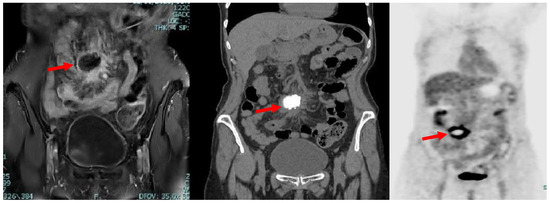

The definitive histological examination is reported below:

“Macroscopically, the surgical specimen consisted of solid nodular fragment, whitish in color, 4 × 3.5 × 3 cm in size, homogeneous in cut surface, partially calcified. Microscopically, Hematoxylin and Eosin stained sections documented extensive fibrosis with dystrophic calcifications and foci of lymphomonocytic, plasma cell and granulocytic infiltrate, mixed with areas of necrosis. To investigate the presence of fungi and/or mycobacteria, histochemistry was performed with Periodic Acid-Schiff (PAS), PAS-D (Periodic Acid-Schiff with diastase), Grocott’s and Ziehl- Neelsen stains in seriate sections. No fungi and mycobacteria were detected. A descriptive final diagnosis of fibro-hyaline nodule with mixed inflammatory infiltrate and suppurative necrosis was made, advising to carry out culture tests and integration with clinical-serological data” (Figure 3).

Figure 3. (A) Extensive fibrosis and dystrophic calcification (Hematoxylin and Eosin, 0.5×); (B) Suppurative necrosis (Hematoxylin and Eosin, 5×); (C) Lymphomonocytic, plasma cell and granulocytic infiltrate (Hematoxylin and Eosin, 20×).